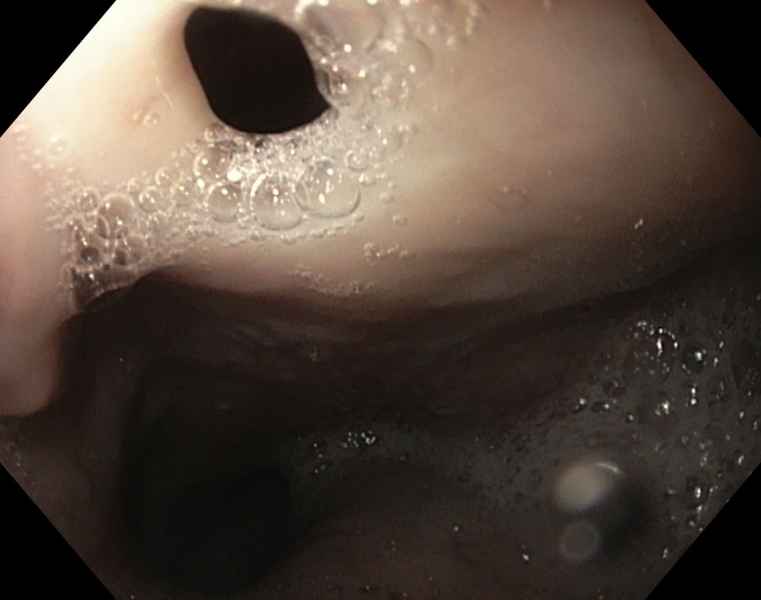

Idiopathic chronic pneumatosis intestinalis: a rare incidental endoscopic finding

Fotografias